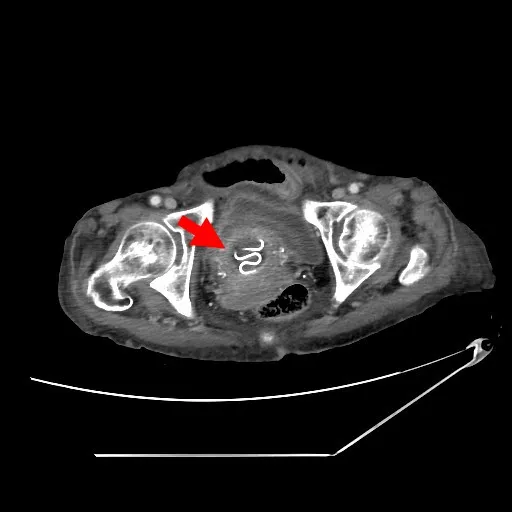

電腦斷層影像中,可看到婦人子宮內的避孕器(箭頭處)。林恩楷醫師提供